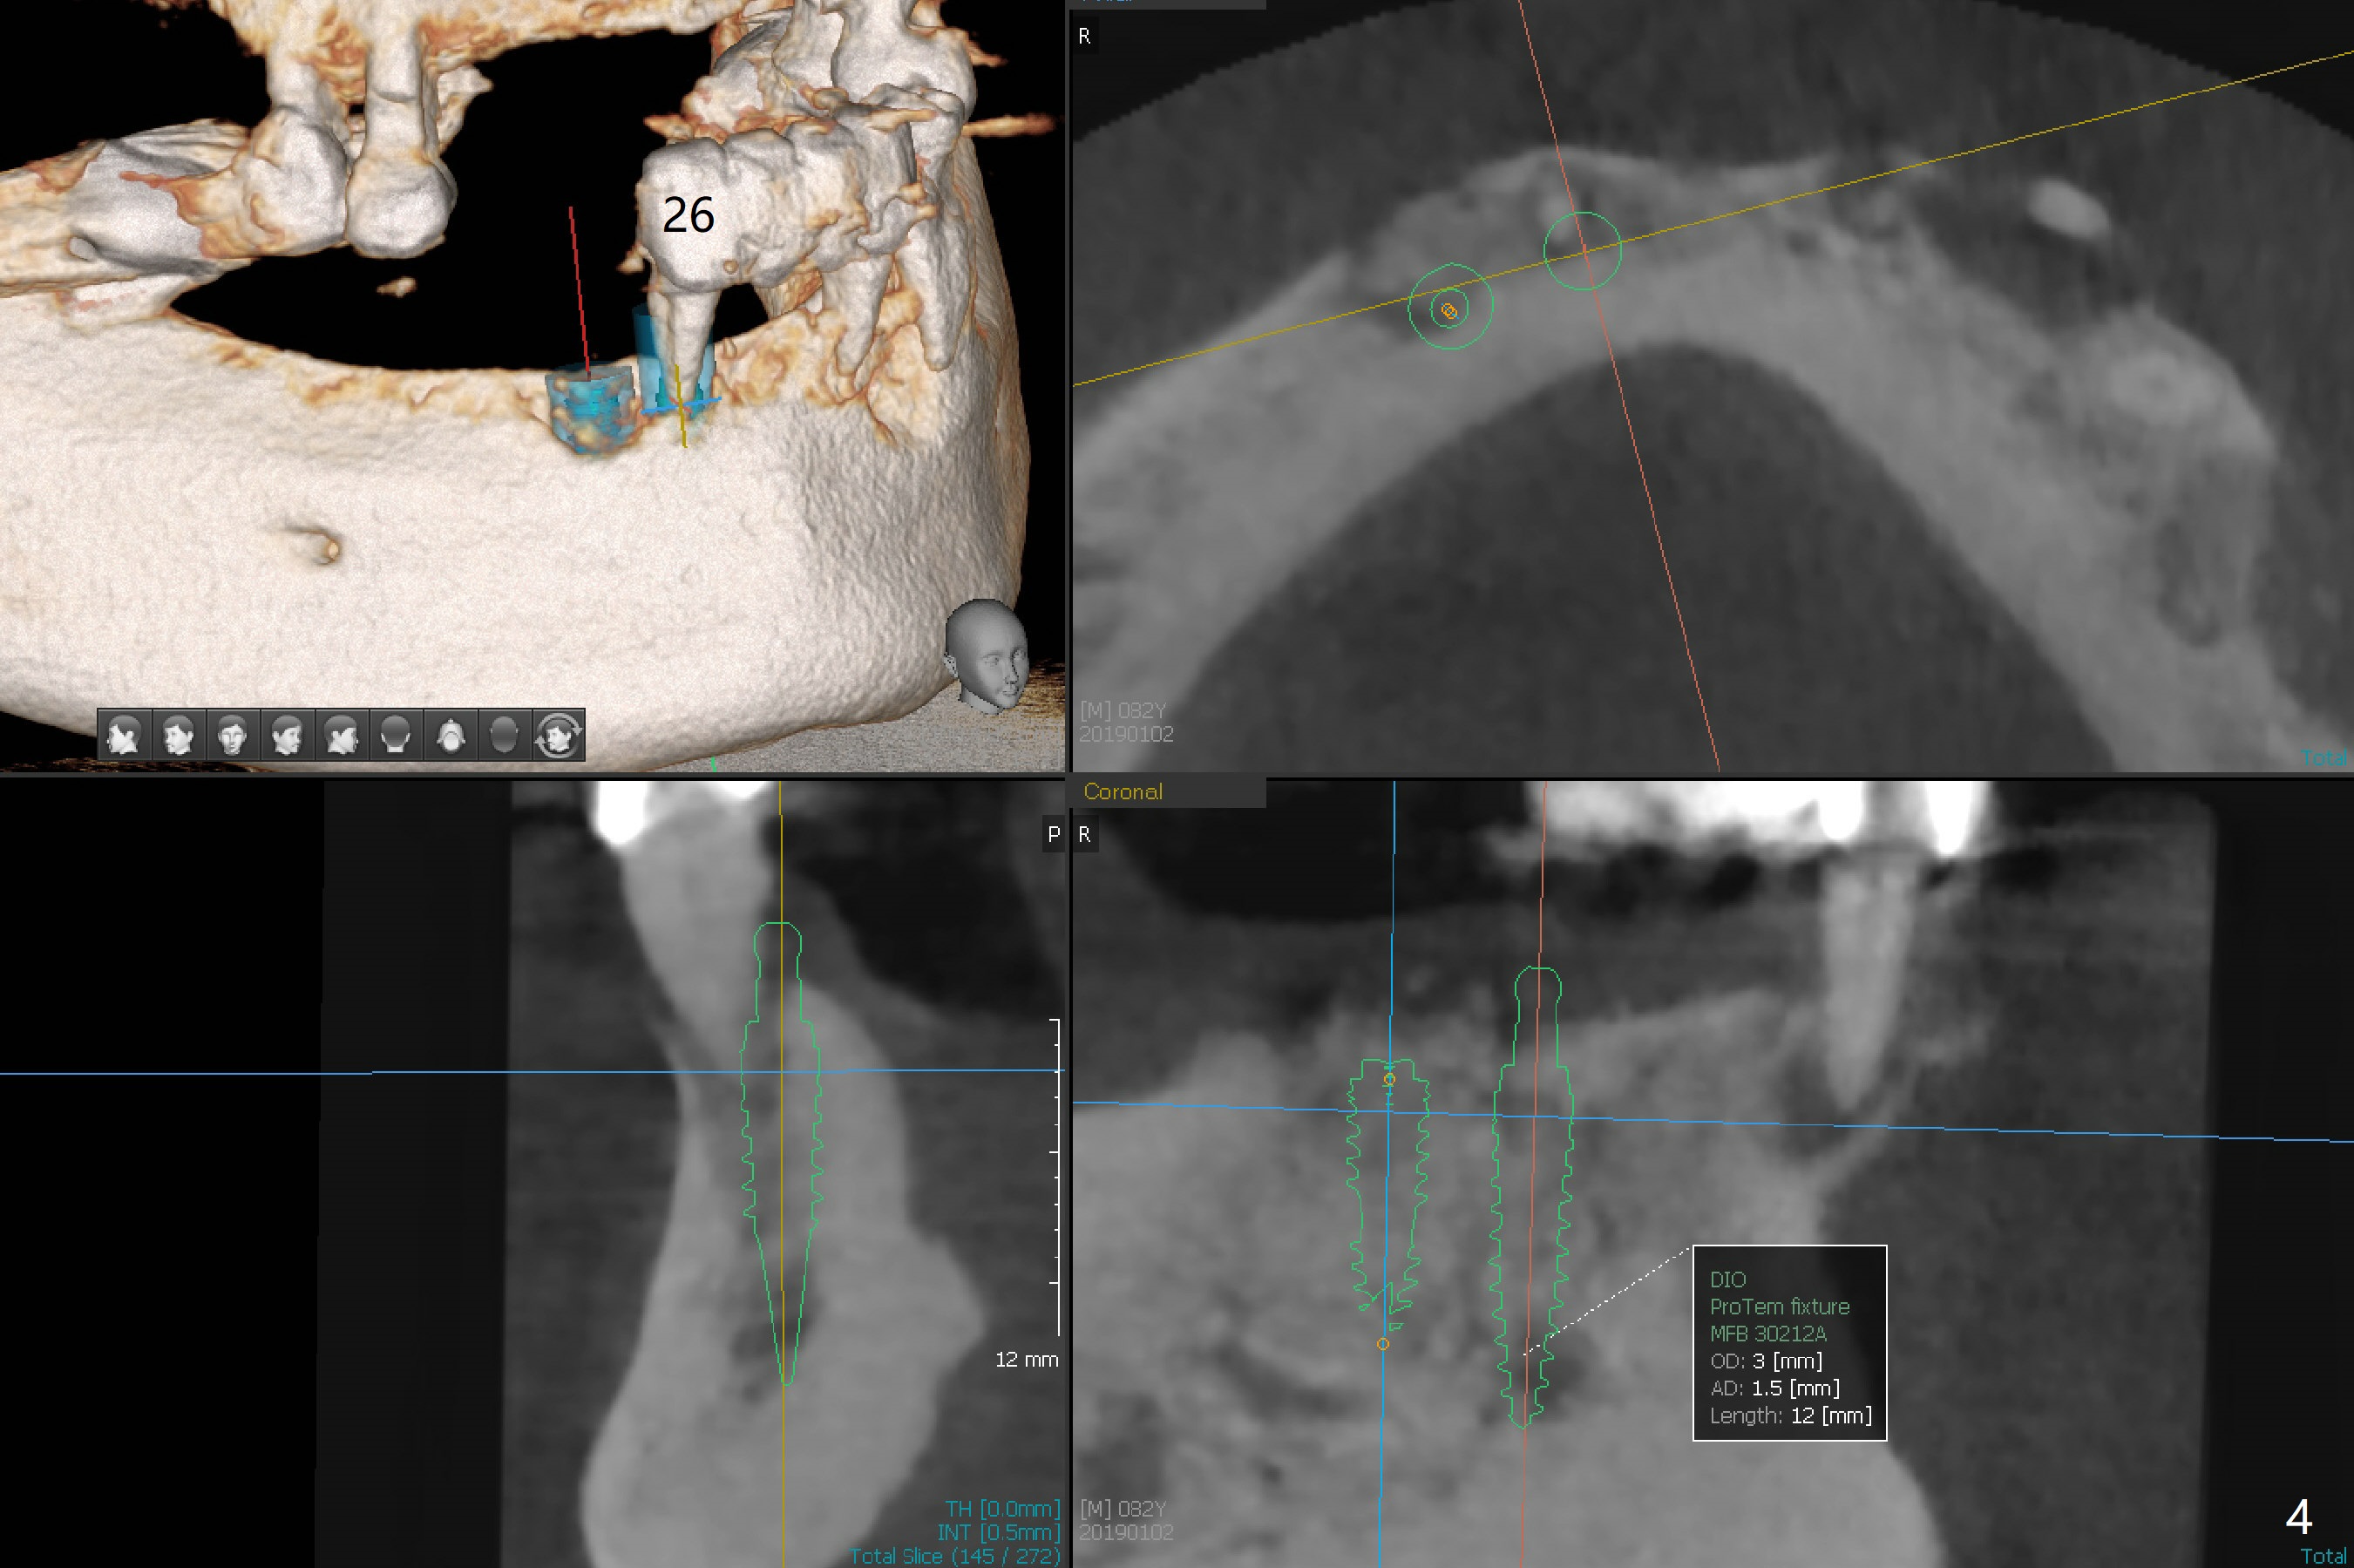

Abutments for Lower RPD

A 82-year-old man with poor dentition (upper and lower RPDs) returns to clinic for definitive treatment 2 weeks post socket preservation at #27 (with loss of the buccal plate, Fig.1). The bridge at #23-26 is mobile and to be removed. The tooth #22 appears to be restorable, but there is a buccal fistula (Fig.2 *). The root is out of the socket revealed by CBCT (Fig.5). Bone loss is severe at #20 (Fig.1,6). Three implants are going to be placed with guide at 27 or 26, 22 and 20 (Fig.3-6) with ball abutments for the lower RPD retention. Later the tooth #18 is found to be nonsalvageable.